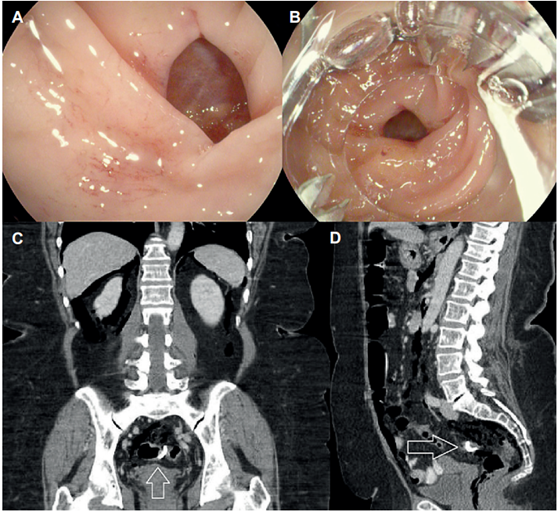

Se manejaron 7 perforaciones agudas y 2 de ellas fueron intencionales, como parte del plan de resección en el caso de tumores neuroendocrinos gástricos con sospecha de infiltración de la submucosa, logrando obtener margen microscópico negativo, el cual se consideró suficiente para el tratamiento de los mismos 10. Las 5 restantes se presentaron de forma accidental, 3 en procedimientos terapéuticos y otras 2 en procedimientos diagnósticos (Figura 1).

Figura 1 A. Perforación a nivel de unión rectosigmoidea durante colonoscopia diagnóstica. B. Visión previa colocación de OVESCO. C. Imagen coronal que evidencia retroneumoperitoneo residual con clip en adecuada posición (Flecha). D. Imagen sagital que confirma éxito clínico temprano descartando extravasación de medio de contraste con clip en adecuada posición (Flecha).